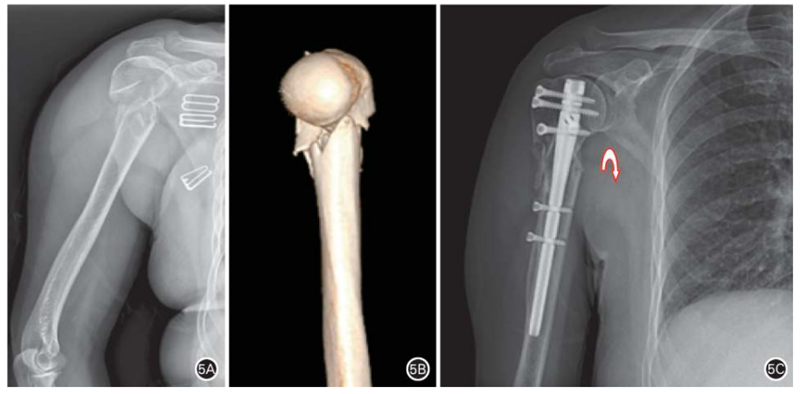

目前,临床使用近端直型锁定型肱骨近端交锁髓内钉治疗肱骨近端骨折。Hessmann等采用多枚交锁螺钉多方向锁定固定肱骨近端,并且设计了“钉中钉”,目的是更好地固定肱骨头。第三代肱骨近端髓内钉可治疗所有类型的肱骨近端骨折。微创髓内钉的优点:(1)对软组织损伤更小,最大限度保留了骨折后残存的血供;(2)术后疼痛程度较轻,功能恢复较快(图4);(3)髓内中心固定肱骨近端髓内钉对抗内翻应力优于髓外偏心固定的肱骨近端锁定钢板(图5)。髓内钉理论上的优势是否能在临床实践中得到体现尚需临床循证医学证据支持。

图5 肱骨近端两部分外科颈骨折,内侧距粉碎性骨折伴移位,行闭合复位髓内钉固定。 A、B. 术前正位X线片及CT三维重建示肱骨近端两部分外科颈骨折,内侧距粉碎性骨折伴移位;C. 术后6个月正位X线片示闭合复位髓内钉固定内侧距解剖愈合,内侧距解剖复位标志是肱骨干内侧至肱骨头关节软骨面下缘的弧线与沿肩胛骨外侧缘至肱骨头关节软骨面下缘的弧线相交成连续弧线(弧形箭头所示)